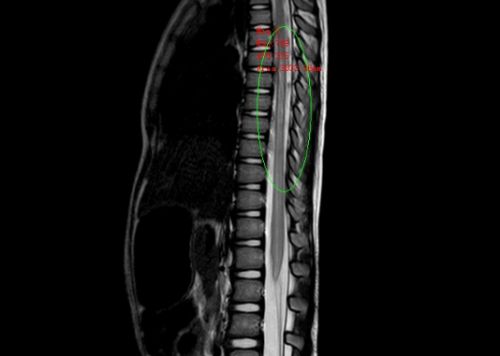

MRI显示:胸腰段脊髓内有异常信号,考虑脊髓损伤。

文捷博士检查发现,琪琪肚脐以下截瘫,双下肢没有感觉、无法活动,大小便失禁。综合体格检查、MRI、CT等检查结果,琪琪被诊断为:脊髓损伤,完全性截瘫。医生当即对她下了病重,随后给予激素冲击治疗及营养神经、消肿、护胃、补液等对症治疗,并请康复科、中医科协助进行针灸、推拿、低频脉冲电治疗等。因为还未过脊髓休克期,后续治疗方案将根据病情决定。